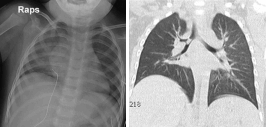

2. 3세 된 소아가 지속되는 발열과 기침, 객담 및 경도의 호흡곤란을 주소로 소아과의원에서 폐렴으로 치료받던 중 호전이 없어 내원하였다. 내원 당시 시행한 흉부 단순 촬영 사진과 경부 전산화 단층촬영 사진이다.

③ 흉부 전산화단층촬영은 민감도가 거의 100%로 매우 높으나 특이도가 66.7~100%로 위양성이 보고된다.

해 설 첫 24시간은 흉부 X-ray가 민감도와 특이도가 가장 낮다. 특별한 기도 이물 흡인 병력이 없더라도 증상과 흉부 CT 소견으로 보아 좌측 기관지의 기도 이물을 충분히 의심할 수 있다. 대부분의 기도 이물은 후두나 기관에 위치하는 경우는 드물며 기관지에 주로 발생한다. 이물질이 기도를 완전히 폐쇄하지 않고 적절하게 호흡이 가능한 환자라면 하임리히 요법 등을 시도하면 완전 폐색을 초래할 수 있으므로 삼가는 것이 좋다.